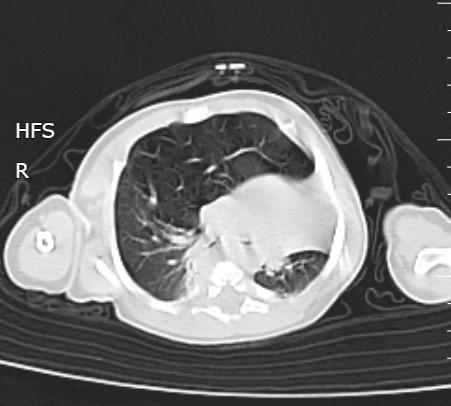

Un nouveau-né âgé de 1 mois est admis aux urgences pédiatriques pour prise en charge d’une détresse respiratoire. Le début de la symptomatologie remonte à la naissance, par l’installation d’une polypnée s’aggravant lors des cris et de l’alimentation, associée à des épisodes de toux sèche. L’examen clinique trouve un nouveau-né tachypnéique, cyanosé avec tirage intercostal et bombement de l’hémithorax droit associé à un wheezing auscultatoire et une SaO2 à 90 % à l’air ambiant. Le patient est mis sous oxygénothérapie et une radiographie thoracique est réalisée, objectivant une hyperaération de l’hémichamp pulmonaire droit refoulant le médiastin (fig. 1). Un scanner est effectué sans injection de produit de contraste et sans sédation, montrant une hyperclarté hypovasculaire avec une expansion du lobe supérieur gauche, refoulant le médiastin et la trachée à gauche, associée à une atélectasie du lobe inférieur droit et de l’hémichamp pulmonaire controlatéral (fig. 2). L’ensemble des éléments radio-cliniques plaident en faveur d’un emphysème lobaire géant compressif congénital (ELGC). Une lobectomie supérieure droite est réalisée, avec une bonne évolution clinique.

En période post-natale, le diag­nostic est plus facile. Sur la radiographie thoracique, le lobe atteint est distendu et hyperaéré, avec une fine trame vasculaire, élément sémiologique essentiel pour différencier un emphysème lobaire géant d’un pneumothorax. Le médiastin est refoulé vers le côté controlatéral et le lobe adjacent est comprimé.5